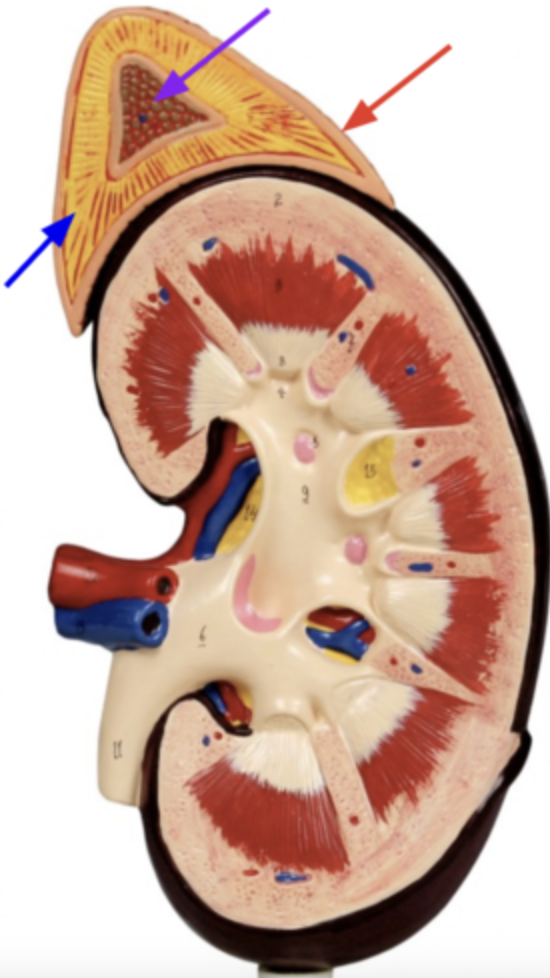

What is the red arrow pointing to?

Capsule

What is the blue arrow pointing to?

Adrenal cortex

What is the purple arrow pointing to?

Adrenal medulla